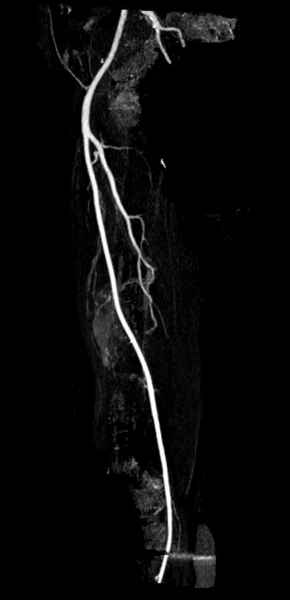

Для предупреждения кровотечения во время рассверливания, за день до операции провели эмболизацию сосудов питающий метастаз. http://radiology.rsnajnls.org/cgi/reprint/150/3/673.pdf (7-11, 12-15-16)

С минимальным рассверливанием и ретроградным методом провели остеосинтез бедра 12 мм гвоздем. (17-20)

Кровопотеря во время операции меньше 100 мл.